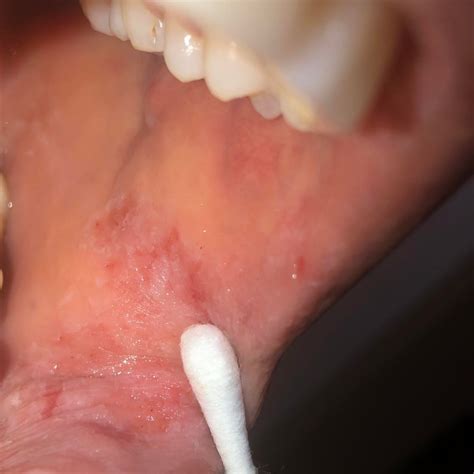

Inside of mouth peeling refers to the shedding or peeling of the mucous membranes lining the inside of the mouth. This condition can affect various parts of the oral cavity, including the cheeks, gums, tongue, and roof of the mouth. The mucous membranes are delicate tissues that protect the underlying structures and help maintain oral health. When these membranes peel, it can lead to discomfort, pain, and potential complications if left untreated.

The symptoms of inside of mouth peeling can vary depending on the underlying cause. Common symptoms include:

• Pain and Discomfort: Peeling of the oral mucosa can cause pain, especially when eating, drinking, or speaking.

• Redness and Swelling: The affected areas may appear red and swollen, indicating inflammation.

• Bleeding: In some cases, the peeling mucosa may bleed, especially if it is traumatized further.

• White or Gray Patches: The peeling areas may have white or gray patches, which can be indicative of infections or other conditions.